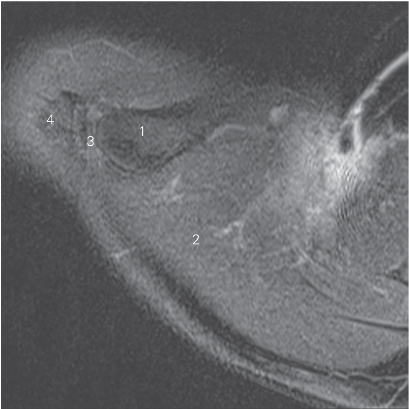

图4-5 经肱骨头上份的横断层MR T2WI FS

1 锁骨 clavicle 2 喙突 coracoid process

3 冈上肌 supraspinatus 4 斜方肌 trapezius

5 肱骨头 head of humerus 6 三角肌 deltoid